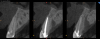

Fig 4. Preoperative CBCT cross-sectional view demonstrating very thin buccal cone.

Figure 4

Fig 8. CBCT at 1-year postoperative demonstrated the retention of the buccal portion of the root as well as maintenance of the buccal plate of bone. Beam hardening and volume averaging artifacts can be noted in the CBCT cross-section.

Figure 8